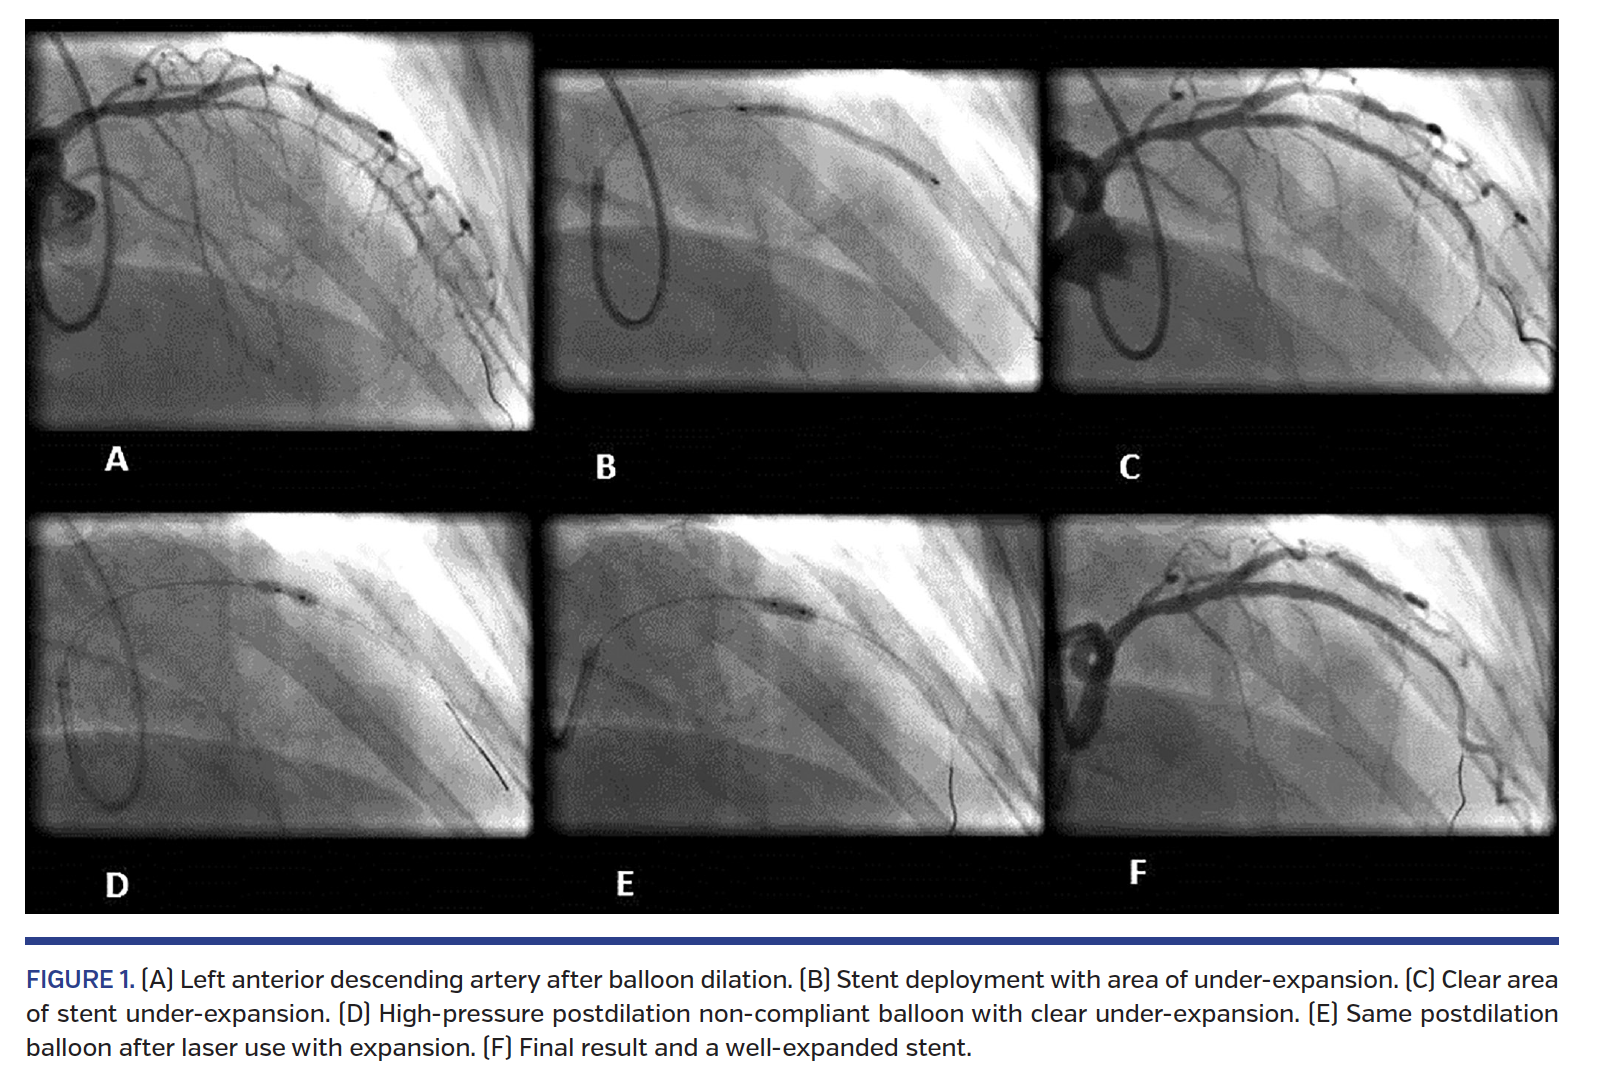

ELCA (Spectranetics) was used with the 0.9 mm laser catheter in 16 cases and 1.4 mm catheter in 3 cases. Laser energy was delivered within the stent at the under-expanded segment in saline medium as a start in all cases. Operator #1 performed laser in contrast medium in 8 out of the 9 cases while operator #2 used contrast in 1 case only. Operator #3 and #4 did not use contrast. The fluence (mJ/mm2)/repetition rate (Hz) varied according to the operator to achieve optimum result in pulses of 40/40, 60/60, and 80/80 with 0.9 mm catheter and 60/40 in the 1.4 mm catheters (Figures 1-4).

After laser use, the under-expanded stent segment was further postdilated to high pressure (16 atm or more) with appropriately sized non-compliant balloon to achieve full expansion. All cases were successful and full expansion was achieved in all but 3 cases where a minor (<10%) under-expansion, identified angiographically, remained despite laser and high-pressure non-compliant balloon inflation. In these 3 cases, laser was performed in saline only and no contrast was used.